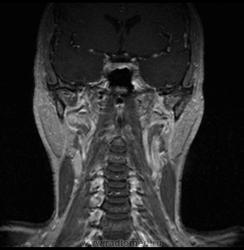

06.06.2011 МРТ - головы и шеи.

Пацентка 36 лет, с жалобами на припухлось в околоушной области справа.

В глубокой доле  правой околоушной железы  на фоне неизмененной паренхимы зона  гетерогенного по Т2, гипоинтенсивного по Т1  с единичными гиперинтенсивными включениями.При контрастировании- накопление контраста диффузное неоднородное и по периферии.Рискну предположить злокачественное образование ( аденокарцинома) с низкой степенью злокачественности( есть капсула, экспансивный рост).Сильно не расстреливайте.

Проблема в том, что перед челюстно-лицевым хирургом стоит распространенность любого объемного процесса, в данном случае все упирается в возмможную травму лицевого нерва и конечно же с дальнейшим его парезом, а ведь женщина  еще молодая. Образование имеет тонкостенную оболочку, по структуре неоднородно, с наличием кальцината, при этом МР-сигнал от окружающих анатомических структур(как костных так и мышечных) не изменен, т.е. об инфильтративном росте речи не идет, в какой то степени доброкачественное. В конкретном случае лицевой нерв с ретромандибулярной веной просто несколько оттеснен.

По гистологии аденома околоушной слюнной железы, но после удаления пока сохраняется парез лицевой мускулатуры, возможно временный.